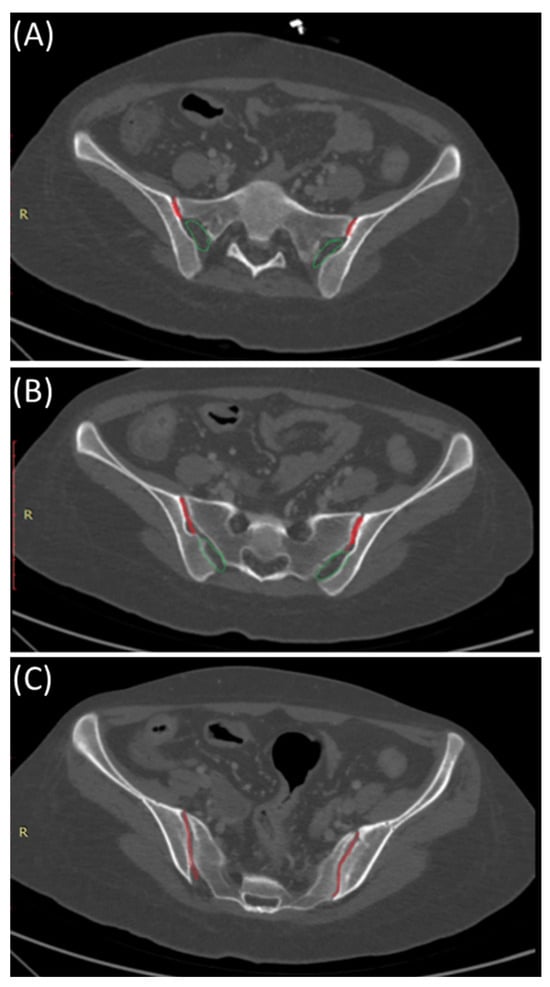

Sacroiliitis is the inflammation of the sacroiliac joint, the largest axial joint in the human body, contributing to 25% of lower back pain cases. It can be detected using various imaging techniques like radiography, Magnetic Resonance Imaging (MRI), and Computed Tomography (CT) scans. Treatments range from conservative methods to invasive procedures. Recent advancements in artificial intelligence offer precise detection of this condition through imaging. Treatment options range from physical therapy and medications to invasive methods like joint injections and surgery.